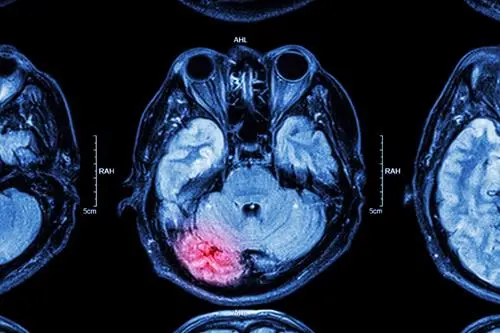

If a TBI is suspected, healthcare providers may use tools such as MRIs, CT-scans, and PET scans to obtain an image of the victim’s brain.

- Computerized Tomography (CT) scans utilize X-rays to create a cross-section and 360-degree image of the brain. This image might reveal brain damage, such as bleeding or bruising.

- Magnetic Resonance Imaging (MRI) utilizes magnetic fields and radio waves to create an image of a person’s brain. MRI can provide images with higher detail than you would get from a CT-scan.